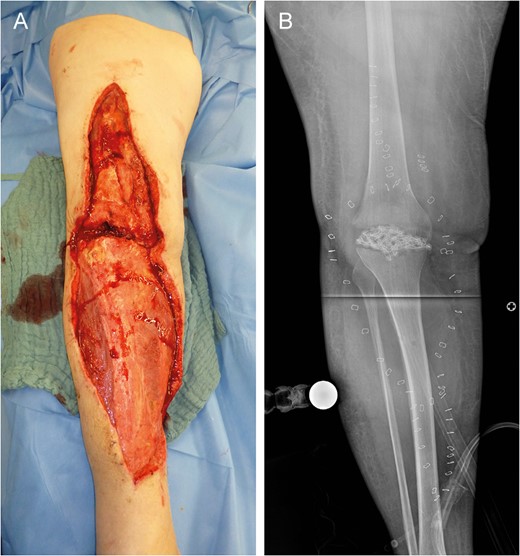

Reconstruction by combined Parascapular (Psc) and latissimus dorsi (Lat) flap with GSV donor site (A). Intraoperative images with pedicle anastomoses (arrows) (B and C).